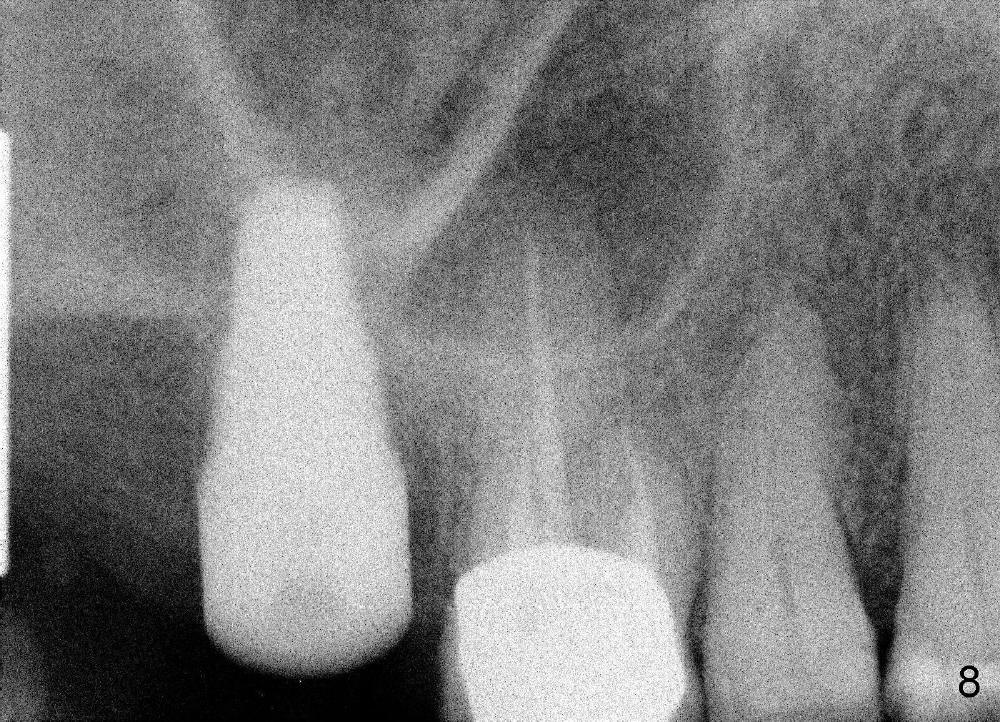

Although the osteotomy appears mainly located in the buccal aspect of the socket apically, the implant (7x17 mm, Fig.8) is placed more or less in the middle of the socket (Fig.9). The trick is to lean the implant palatally while it is being inserted.